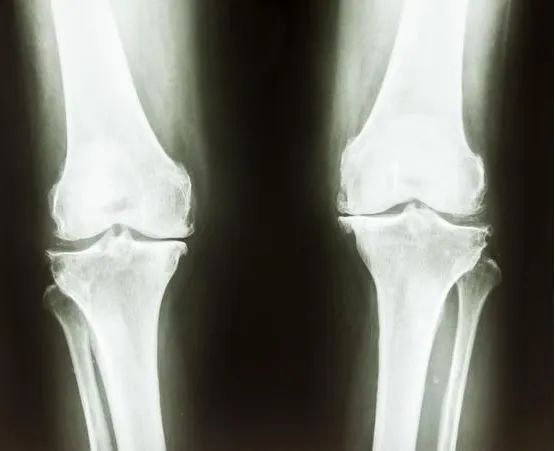

◆左手腕掌指进行X光检查:以了解骨龄,判断骨骺发育程度和生长潜力。